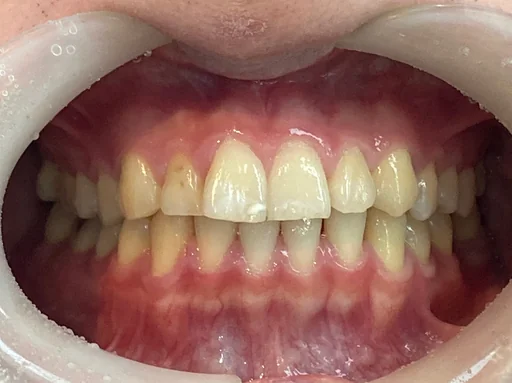

症例1

治療前は歯の重なりやガタつきが気になる状態でしたが、インビザライン治療により、歯列が整い、口元の印象が大きく改善しました。

金属の装置を使用しないため、治療中も自然な見た目を保てる点が、インビザラインの大きなメリットです。

「矯正していることを周囲に気づかれたくない」という方にも選ばれています。